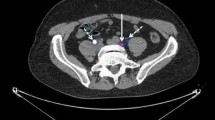

As the first step towards clinical translation of uPAR PET imaging, we have conducted and reported the first-in-humans trial of 64Cu-DOTA-AE105 (ClinicalTrials.gov: NCT02139371). By definition, the primary endpoints of a phase I clinical study are safety, biodistribution, and dosimetry assessment based on three successive PET scans performed at 1, 3, and 24 h post injection. We included total of ten patients with urinary bladder (three patients), breast (three patients), and prostate cancer (four patients). Importantly, no adverse events or clinically detectable pharmacologic effects were found. Radiation dosimetry analysis estimated an effective dose of 0.0276 mSv/MBq, closely resembling the predicted effective dose from our previous mouse study [43], and equaling 5.5 mSv for a 200 MBq dose, which is lower/comparable radiation dose to the dose received from a standard FDG-PET [44]. Secondary objectives were to investigate the uptake in primary tumor lesions and potential metastases. Four patients with newly diagnosed and biopsy-proven PC (mean age 68, Gleason score 7–9) were uPAR PET scanned prior to surgical pelvic lymphadenonectomy for staging and prostatectomy if indicated. In all four patients, a high and specific uptake in the primary intraprostatic lesion was found (Fig. 3). Histopathological examination of three available surgical specimens confirmed a general pattern of uPAR expression in the primary tumor, supporting target-specific uptake of 64Cu-DOTA-AE105. One patient had several visible uPAR PET positive lymph nodes in the pelvic region, which was confirmed during the staging operation and the following histopathological assessment confirmed prostate adenocarcinoma in three out of six removed lymph nodes (Fig. 3). Two patients had no signs of metastases on neither uPAR PET nor perioperative staging, while the last patient was found to have a metastasis in 1 out of 17 regional lymph nodes that were not visualized on uPAR PET or CT. The results of this phase I study was encouraging with uPAR PET being able to identify both primary tumors and lymph node metastases in PC, although the limited number of patients precludes an evaluation of uPAR PET in the initial staging of PC. We have recently conducted another new phase I study, where safety, pharmacokinetics and dosimetry of a 68Ga-labeled version of AE105 (68Ga-NOTA-AE105) are being investigated in cancer patients (ClinicalTrials.gov: NCT02437539), and data are currently under evaluation.

uPAR PET imaging of patients with newly diagnosed prostate cancer. Representative transverse CT, PET, and co-registered PET/CT images from the first-ever uPAR PET study in humans. Upper panel shows a primary tumor lesion (blue arrow) with high uptake of 64Cu-DOTA-AE105. uPAR immunohistochemistry on surgically removed prostate cancer tissue confirmed general pattern of uPAR expression. Bottom images show a uPAR-positive regional lymph node metastasis (blue arrow) with high 64Cu-DOTA-AE105 uptake. The subsequent staging operation and histopathological assessment confirmed prostate adenocarcinoma in three out of six removed lymph nodes.